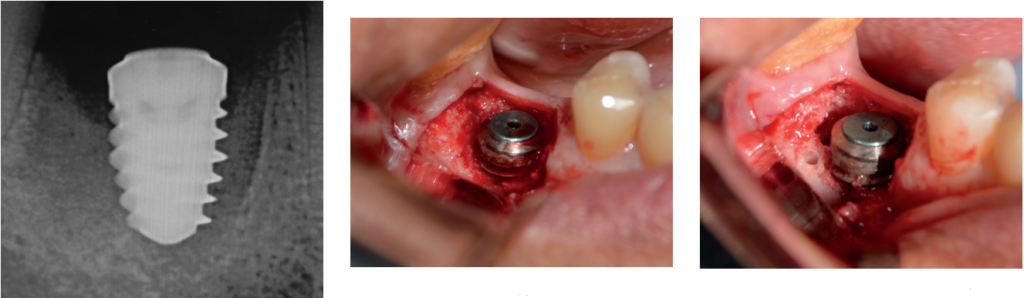

Рисунок 1: 1,5 месяца после установки имплантата

Рисунок 2 (слева): Рентгенограмма через полтора месяца после операции; Рисунок 3 (в центре): Отражение, сохраняющее сосочки; Рисунок 4 (справа): Полное отражение с дегрануляцией кости

В последствии мы столкнулись с потерей костной массы и последующей потерей мягких тканей (рис. 1). Коллагеновая мембрана растворилась из-за суровых условий полости рта. Как только это происходит, биопленка загрязняет шероховатую поверхность имплантата, и затем потеря кости или мягких тканей будет продолжаться дальше. Рентгенограмма показала текущее состояние имплантата (рис. 2), на лицо явная потери костной массы.